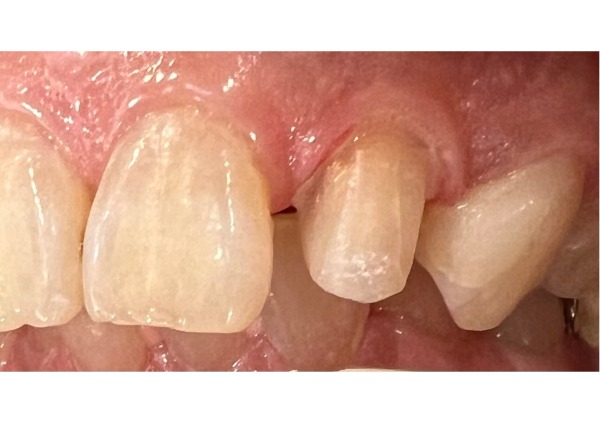

6日目 前歯の虫歯は神経に近いほど大きく、痛みが出たら神経を取る可能性を説明し、左上2番をプラスチックで修復しました。隣り合う歯である左上3番も虫歯になっていたため、同時にプラスチックで修復しました。

7日目 前歯の虫歯治療から約2ヶ月後、前歯で噛むと痛みを伴うことから、左上2番の神経を取る治療を行いました。

前歯の見た目にもご満足いただいています。